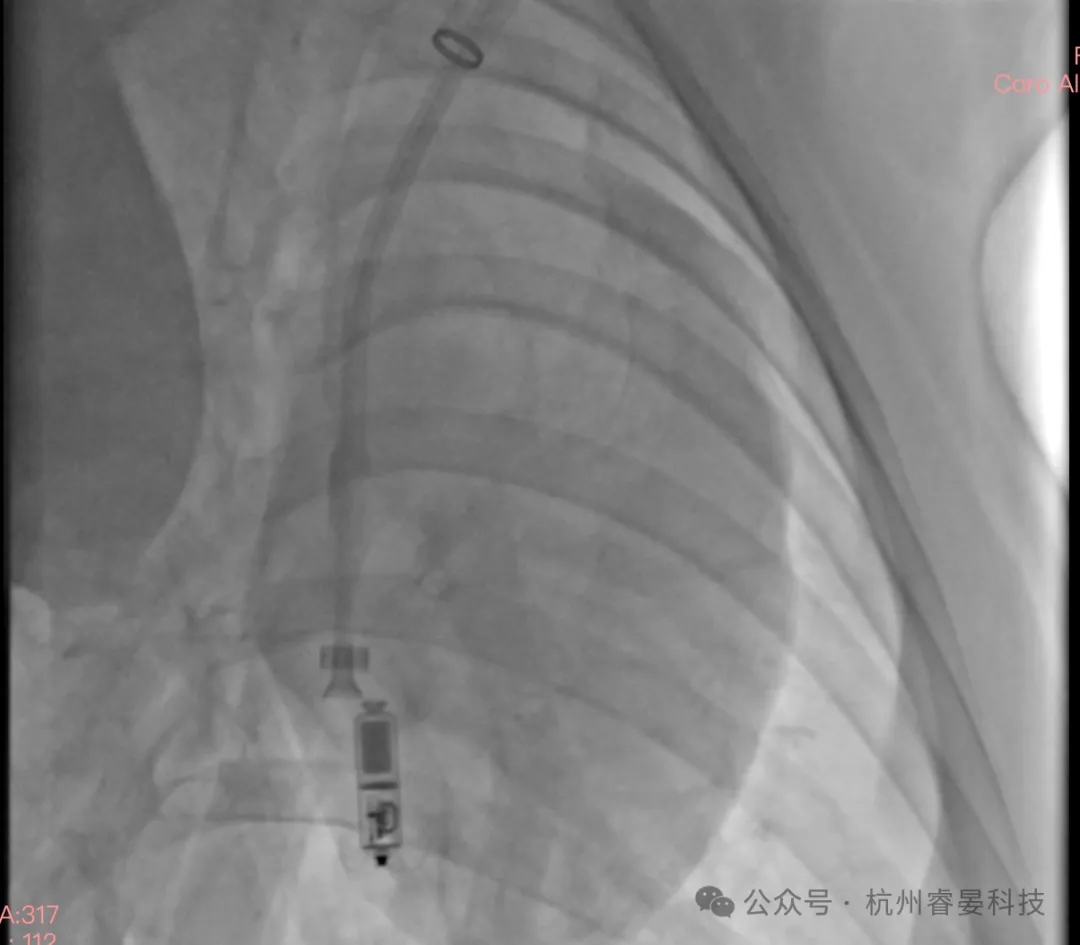

在最终实操环节中,学员在 DSA 引导下,完整体验无线起搏器从输送至释放的全过程,包括:

每位学员平均完成 2 次无线起搏器植入与释放操作,在真实心脏环境中直观感受器械释放时的力学反馈及位置变化,加深了对植入安全边界与操作细节的理解,为后续临床应用提供了重要经验积累。